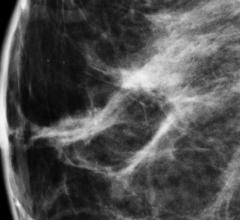

Breast density, or fibroglandular density, is found through breast imaging and compares the amount of fat to the amount of tissue.